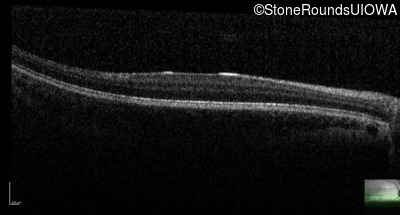

Optical Coherence Tomography - Left - 20/63 -2

Exemplar / OCT Stack

OCT Stack